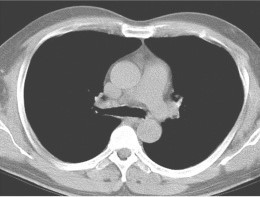

With COVID-19 tests being carefully rationed out and there being multiple scarcities, patients may not have access to a traditional test. Our software can diagnose a patient purely on a CT scan, eliminating the need for single use tests. We used the COVID-19 Lung CT Scans by LuisBlanche on Kaggle.

Our web app has a form for submitting patient data and uploading a CT scan image. We then pass the pixel data to our server, which runs several Tensorflow models. We then take the average confidence of all the models, and return the prediction to the browser. You can test it with the CT Scan images in the Devpost Gallery.

We built 8 Deep Learning Models with Tensorflow and Keras that integrate convolutional neural network architecture and was trained using K-fold Cross-validation, in order to make best use of a limited dataset. Our model achieved nearly 90% accuracy, allowing hospitals to use this as a tool to diagnose patients when resources are limited.